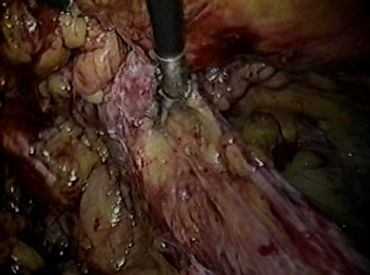

During keyhole surgery, the surgeon usually makes 3 small incisions in your abdomen instead of a single larger incision.

A thin tube containing a light source and a camera (laparoscope) is inserted through one of these incisions so the surgeon can see inside your abdomen.

Special surgical instruments are inserted through the other incisions so the surgeon can pull the hernia back into place.